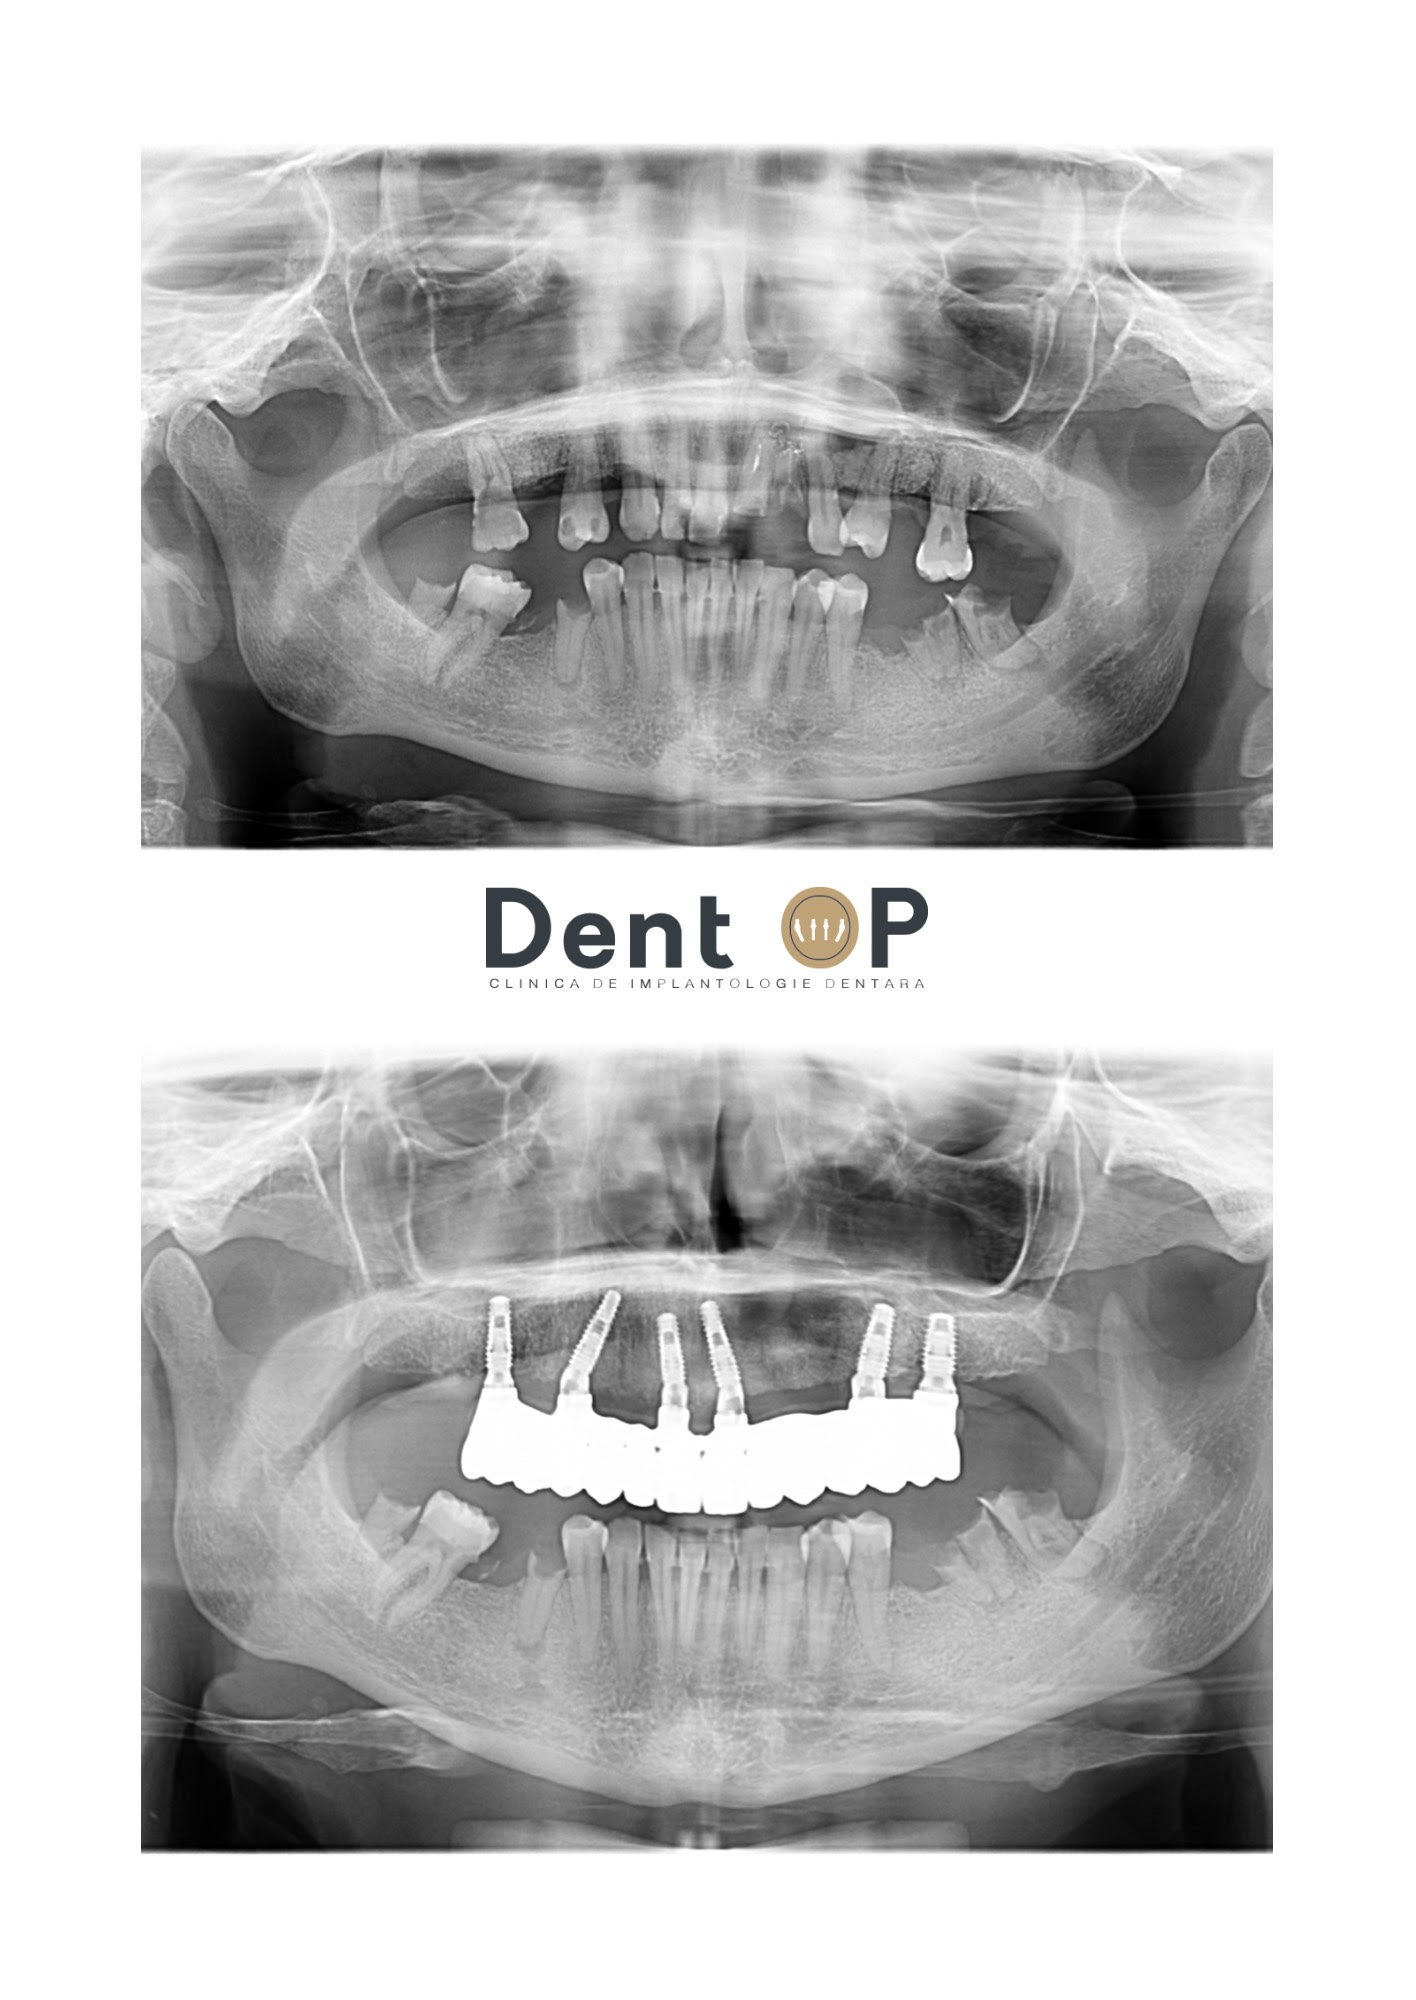

Încă din cadrul primei consultații, Dr.Cazacu Corrado a observat că pacienta noastră avea un chist la maxilar destul de mare. Pe lângă această problemă, mai mulți dinți au fost afectați de carii și de alte traumatisme.

Dr. Cazacu Corrado a stabilit un plan de tratament adecvat și după o discuție cu pacienta noastră, s-a decis inserarea a 6 implanturi dentare într-un mod special evitând zona chistului și cu reparație de os.

După 6 luni, pacientei i-au fost inserate lucrările definitive pe acele implanturi, iar acum se bucură de o dantură perfect sănătoasă și frumoasă.